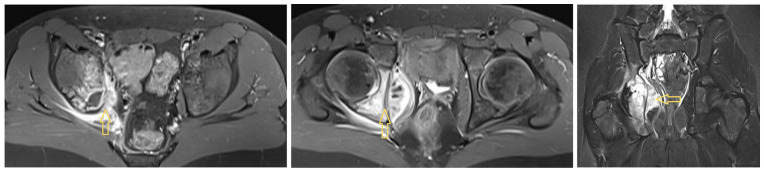

Background: In paediatric osteoarticular infections, microorganism detection is unsuccessful in up to 55% of cases, which is not satisfactory for targeted antibiotic therapy. In particular, anaerobic fusobacteria may be underdiagnosed owing to a lack of knowledge about their properties. Methods: Based on three of our own cases and a systematic literature review regarding paediatric osteoarticular fusobacterial infections, we extracted characteristic variables and synthesised them in terms of frequencies and mean comparisons. We followed the CARE and PRISMA guidelines. Results: In our three patients with hip area infections (aged 11, 12, and 16 years; two males and one female; two with Fusobacterium nucleatum [FNU] and one with Fusobacterium necrophorum [FNE]), we only detected FNU with PCR. The patient with an FNE infection showed a septic and protracted course with six surgical interventions and secondary coxarthrosis during the follow-up. The FNU infections were milder and healed without sequelae. In the literature, there are no articles with more than 3 cases; overall, we identified 38 case reports and 3 case series with a total of 45 patients. Across all synthesised cases (73% boys), the age was 9.2 ± 4.1 years. Most patients (42%) were affected by hip joint arthritis, with or without accompanying acetabular or femoral osteomyelitis, followed by knee joint arthritis, with or without osteomyelitis, in 24% of patients. In 49% of cases, there was an ear, nose, and throat focus. Depending on the affected structure, arthrotomy (33%), arthroscopy (11%), bone (24%), and soft tissue (9%) debridement were performed, with 34% of the procedures having to be performed several times. Penicillins, metronidazole, and clindamycin were the most used antibiotics. In 32 cases (71%), the authors reported healing without sequelae. Conclusions: When samples are collected in the operating theatre for paediatric osteoarticular infections, orthopaedic surgeons should also ensure correct anaerobic sampling and consider the possibility of performing PCR. A typical child with an osteoarticular fusobacterial infection is a boy of approximately 10 years of age with an infection in the hip area and a previous infection in the ENT area.